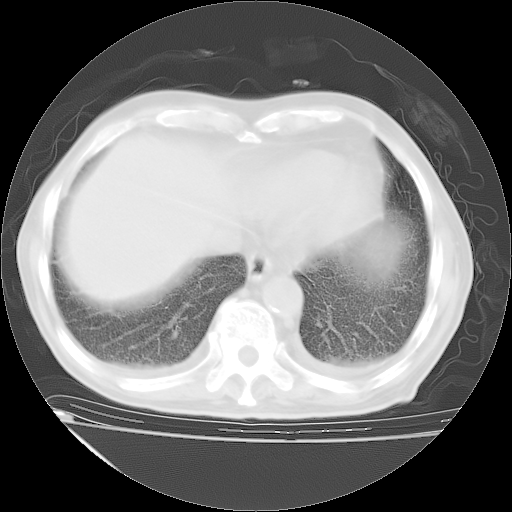

甲强龙80mg/日+抗结核治疗(异烟肼+利福霉素+乙胺丁醇)10天。复查肺部CT。

治疗10天肺部CT

补充下:5月9日胸部CT:似乎已见双下肺胸腔积液了,鉴于目前有下肢水肿,肝功示:白蛋白低,应注意多浆膜腔积液(漏出液可能大?),需注意!